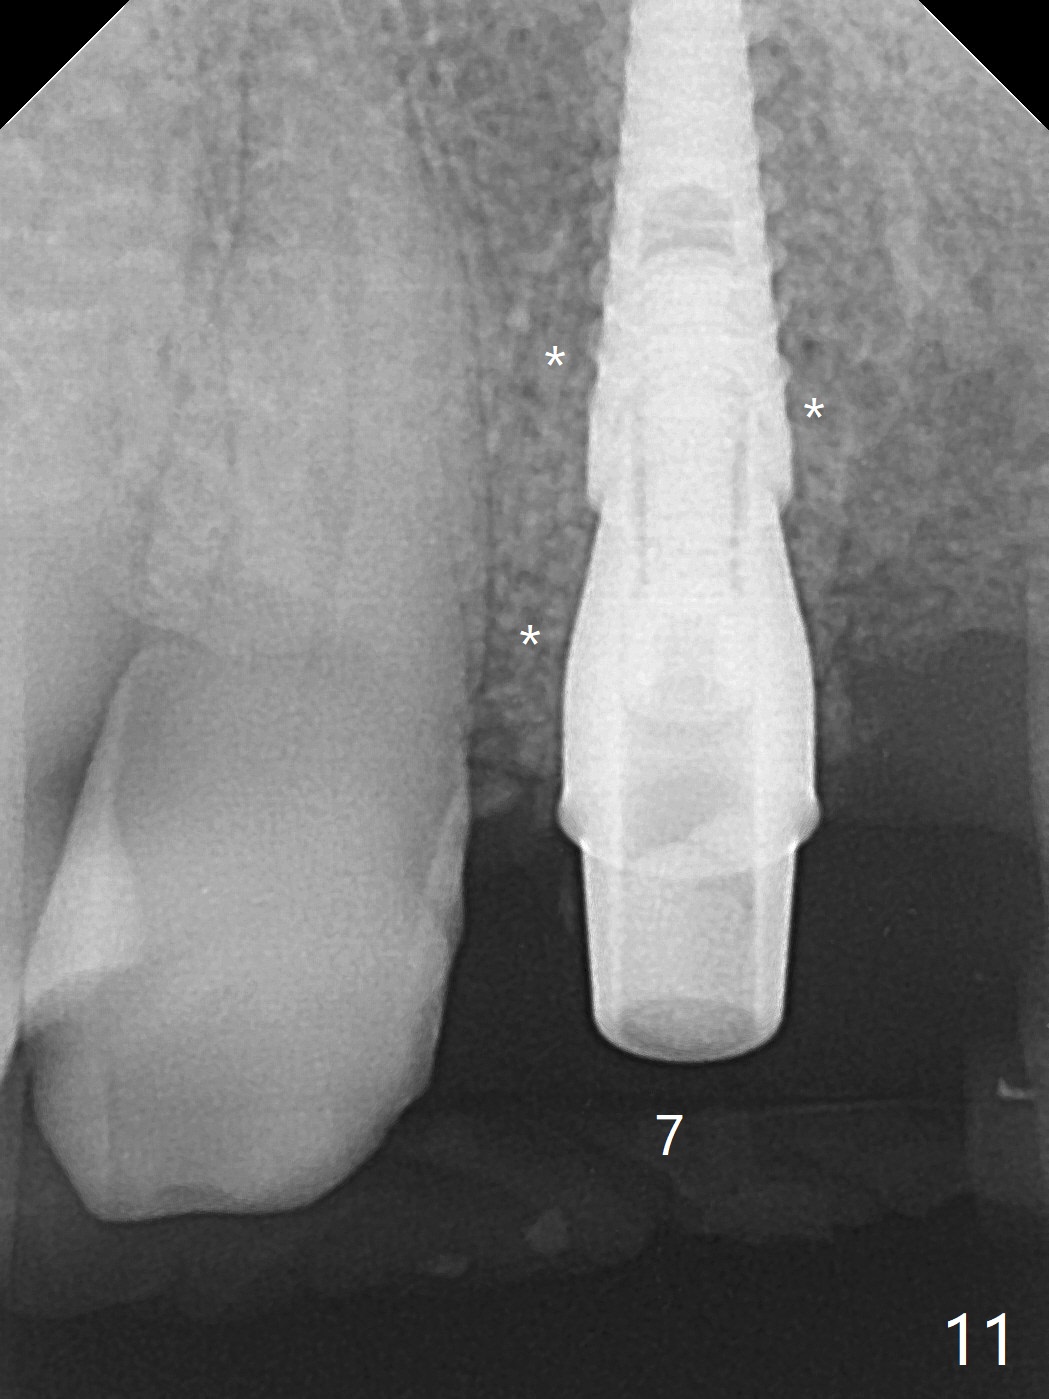

今天下午进入治疗室,粘性骨粉已制备:上清液来自红管(含促凝剂),离心3分钟(图一);再离心10分钟上清液就转变PRF,压制后,使用前剪成三块(图二:黑线),其中两块punch一个洞(图二:圆圈),插入7,9号牙基台固定;大块覆盖11/12号牙牙槽窝(图十四)。7,9,11,12号牙必须拔除(图三),然后在7,9,12种植。由于缺失左下磨牙,前牙垂直距离减少(图四)。完成9号牙位钻洞后,利用fixture mount(图五:M)植入植体,并留在原位固定导板(图六),然后7号牙种植,也留下fixture mount(图六:7,9),最后完成12号牙植入,但是后者扭力低,放置愈合螺帽(图九),而7,9号牙位放置修复基台(图七,八(使用5.5毫米profile drill后),好像基台没有完全就位。7号牙位更换基台似乎没帮助(图十),9号牙位再次放置同一个基台临床上仿佛有改变(比较图八与十二)。放置粘性骨粉后(图十一至十三),牙槽窝口覆盖PRF膜(图十四:P(A:基台)),最后使用树脂敷料固定骨粉和膜(图十五,六),基台帮助敷料固位,没有咬合干扰(图十七:*)。树脂敷料部分解决美观问题,一个月后撤除,如果植体仍有稳定性,可能制作7-10临时牙桥,可能部分维持或者恢复牙龈外形。术后一周病人主诉后面植牙和鼻底疼痛,11号牙根尖牙龈充血(图十八),轻度触痛,可能与术中尚未完全清创有关(图十九(术前CT 3D图像))。再服用Amoxicillin一周,症状好转,鼻底轻度触痛(图二十)。术后1.5月没有任何不适,撤除树脂敷料,7号牙基台(袖)显得太长,换一个短的(4.5x4(5)(图十,十一)->4x4(3)毫米)毫米),植骨好像愈合正常(图二十一:*)。7号牙换了短的基台,9号牙基台高度调整后,与对合牙有足够空间做临时牙桥,最好8,10号牙位牙龈应该凹陷(图二十二:*),有pontic外形。另外9号牙基台颊侧牙龈边缘有所修整,临时牙桥准备。先做7-10临时牙桥,理想临时牙桥pontic处树脂应该多些(图二十三:白线)压迫牙龈形成凹陷。11,12号牙牙槽窝在树脂(Bosworth)敷料下也正常愈合(图二十四)。